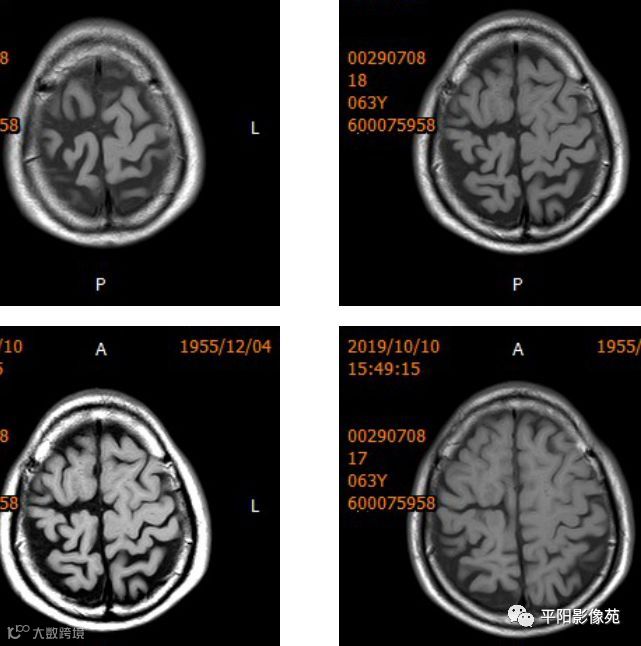

右侧额叶中央前回局部脑裂增宽,并向内延伸,周围衬以等灰质信号,呈稍长T1稍长T2信号,病灶自软脑膜向内延伸,与室管膜相连。